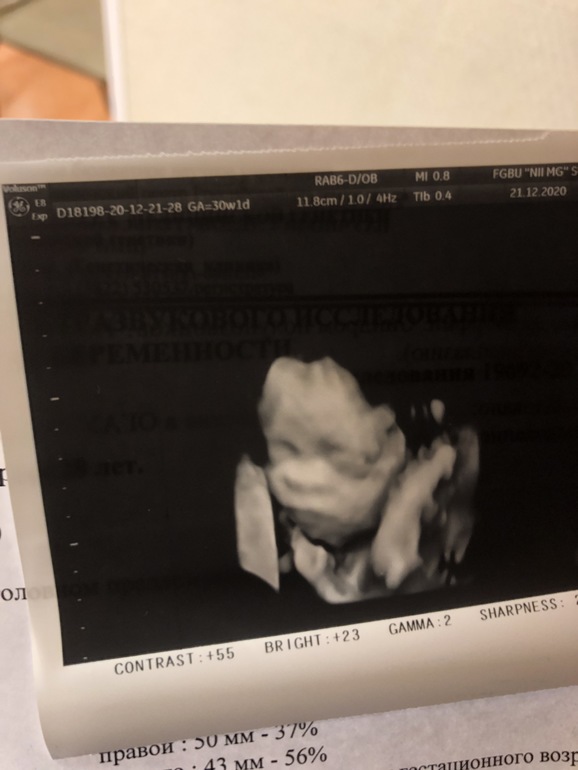

Наш «безносый» 3 скрининг. Фото

Ну что, прошли мы третий скрининг.

В 25 недель по прежнему не видели нос.

Но наш малыш вырос!

Даже опережает на 1 день теперь 😂

Вес 1,5кг

Нос вогнут, но он есть😅

Лежал, зевал🙏🏼

Ну и наши фото))